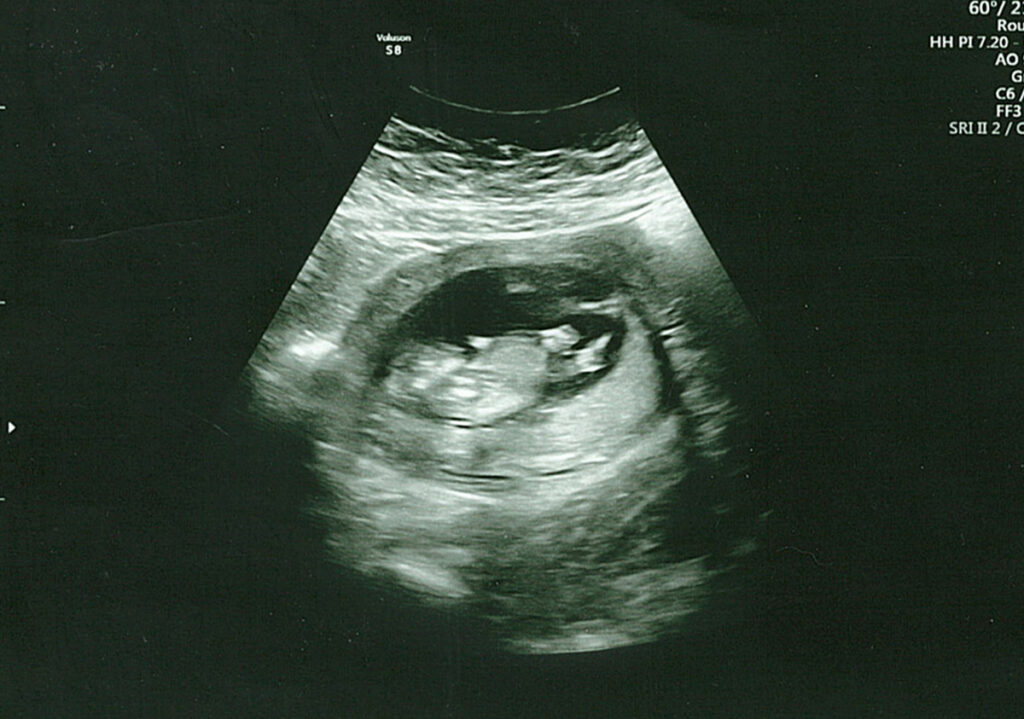

I’m happy to report the visit went amazing, and we couldn’t have asked for a better ultrasound tech. She first let us hear the heartbeat and even spent extra time with us, trying to get better photos (though I need to drink more water). She let us record the visit, and I’ve included a few pictures and a short video clip showing our baby moving around. Life is such a miracle, and seeing this baby, the size of a lime, move around was incredible.

This pregnancy – Video Clip from Our 12 Week Ultrasound

Here’s a short clip from our visit where you can see our baby moving around. This visit was exactly what we needed, and I feel even more connected to this little human, though it’s still crazy to think they’re growing inside my body.